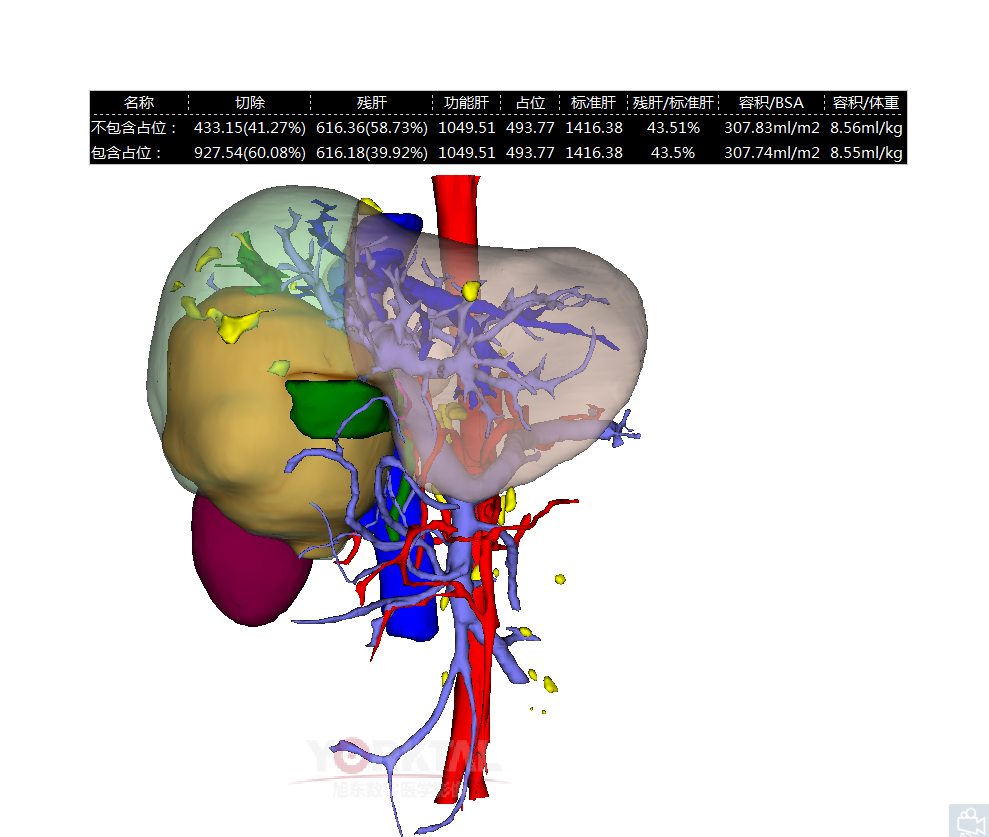

術前三維重建虛擬手術規劃

車旭主任安排了相關檢查評估,利用術前三維重建技術,進行了虛擬手術規劃,認為患者雖然腫瘤巨大,但通過精細操作選擇性保護殘肝組織,仍有根治性切除的可能。謹慎起見,他又聯繫了蔡建強副院長進行會診,並邀請了醫院知名肝膽外科專家畢新宇教授參加會診和共同手術。